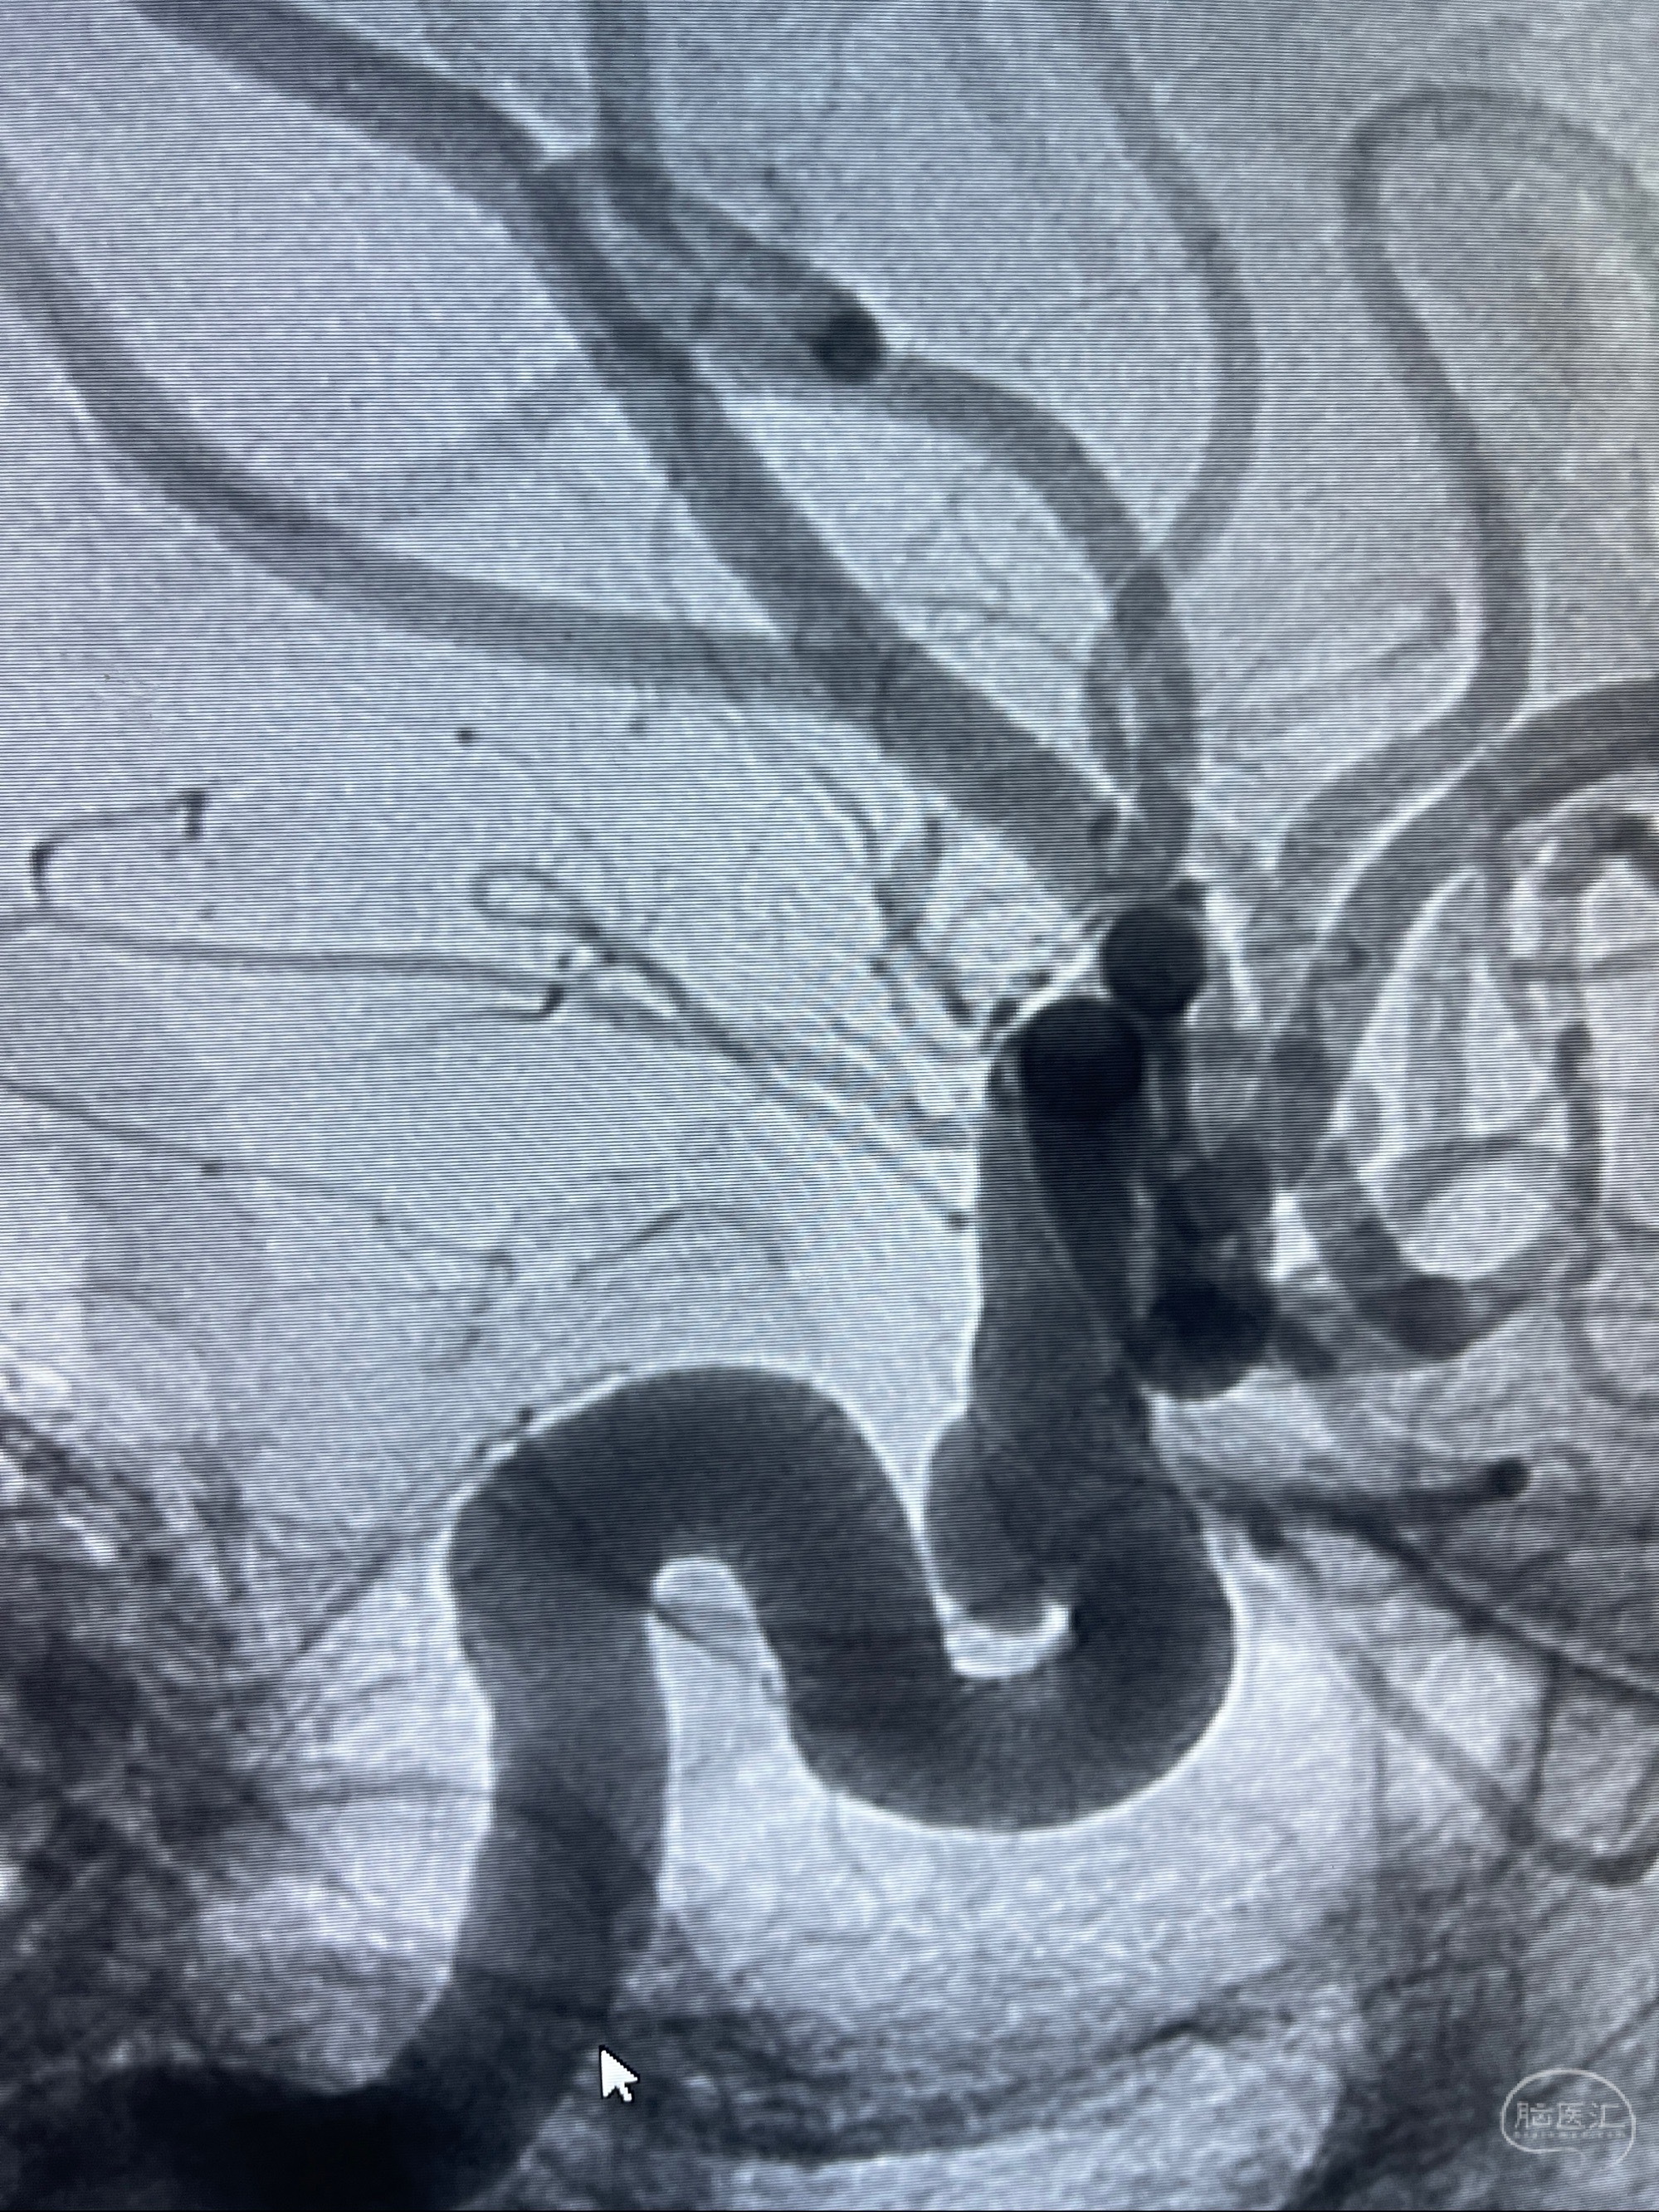

2023-07-27全脑血管造影:双侧颈内动脉眼动脉段动脉瘤,右侧较大

2023-08-01全麻下行双侧颈眼动脉瘤支架辅助栓塞

- pipeling4.5-20mm

- pipeline 4.0-20mm

手术顺利,麻醉苏醒佳,遵嘱动作